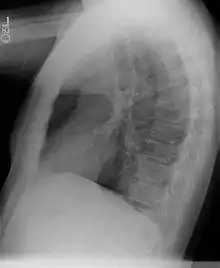

Chest radiograph

- Sequestrations typically appear as a uniformly dense mass within the thoracic cavity or pulmonary parenchyma.

- Recurrent infection can lead to the development of cystic areas within the mass.

- Air-fluid levels due to bronchial communication can be seen.